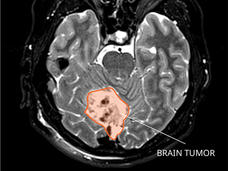

Test Detects Early Signs of Remaining Cancer in Kids Treated for Medulloblastoma

A new test could potentially be used to identify children treated for medulloblastoma who are at high risk of their cancer returning. The test detects evidence of remaining cancer in DNA shed from medulloblastoma tumor cells into cerebrospinal fluid.